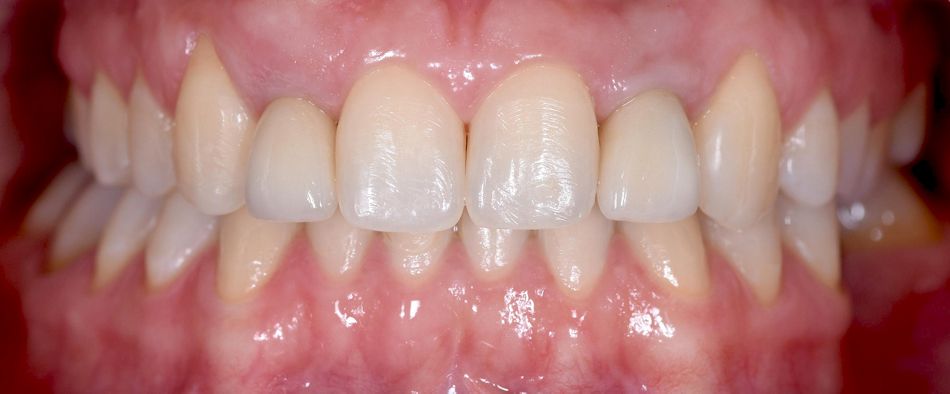

The connective tissue graft from the tuberosity led to a stable result with an increase in soft tissue volume. (Fig. 31-32)

The final images show the clinical situation at 16 months of follow-up after implant insertion. A periapical radiograph was taken using a Kodak RVG 5200 sensor (Carestream®) during this visit, in which it is possible to see the stability of the tissues. (Fig. 33-34)

Here we used a Straumann® BLT Ø 2.9 mm implant in a narrow interdental gap and unfavorable interradicular space combined with mucogingival surgery and the placement of a provisional crown before the insertion of the final crown. The implant resulted in a successful outcome, improving soft tissue stability and esthetics.